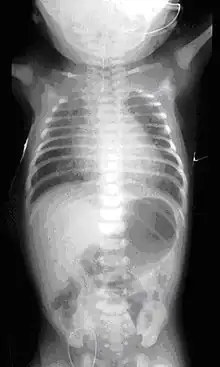

On plain X-ray, a feeding tube will not be seen pass through the esophagus and remain coiled in the upper oesophageal pouch.[8]

If any of the above signs/symptoms are noticed, a catheter is gently passed into the esophagus to check for resistance. If resistance is noted, other studies will be done to confirm the diagnosis. A catheter can be inserted and will show up as white on a regular x-ray film to demonstrate the blind pouch ending. Sometimes a small amount of barium (chalk-like liquid) is placed through the mouth to diagnose the problems. However, performing such an oral contrast study is not advised due to a risk of aspiration.[27]